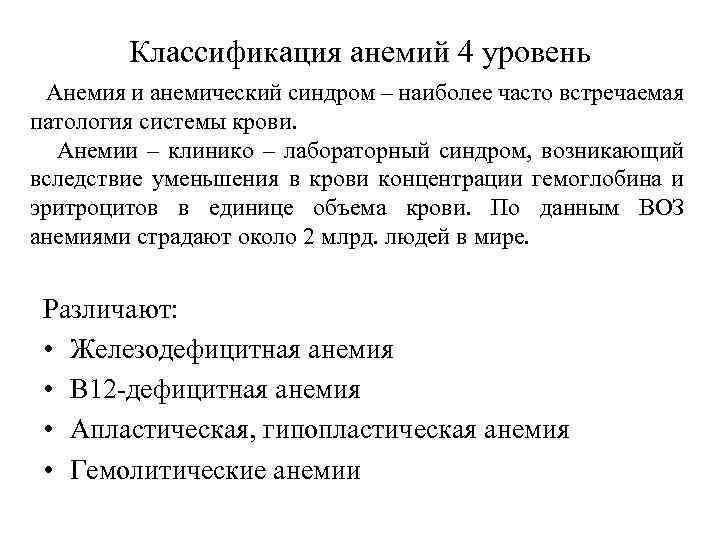

Классификация анемий 4 уровень Анемия и анемический синдром – наиболее часто встречаемая патология системы крови. Анемии – клинико – лабораторный синдром, возникающий вследствие уменьшения в крови концентрации гемоглобина и эритроцитов в единице объема крови. По данным ВОЗ анемиями страдают около 2 млрд. людей в мире. Различают: • Железодефицитная анемия • В 12 -дефицитная анемия • Апластическая, гипопластическая анемия • Гемолитические анемии